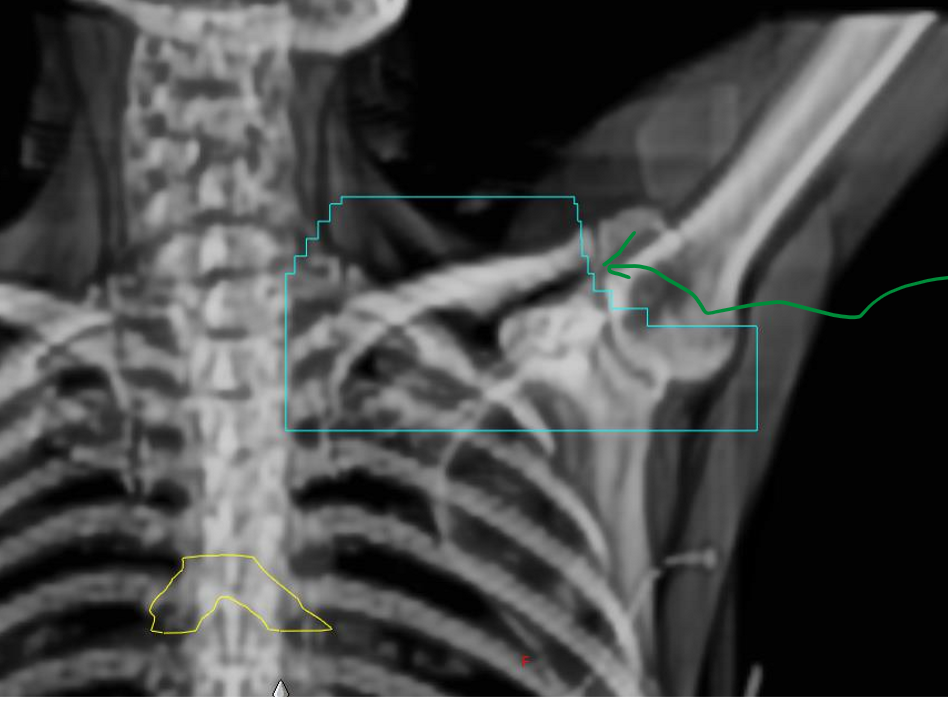

what are the MLCs the arrow is pointing to shielding?

we are shielding the thyroid

what two lymphatic nodes are being included in the BEV?

we are shielding the acromioclavicular joint

two nodes: supraclavicular and axillary nodes

on a supraclav BEV, what three thing are we assessing?

arm position (see clavicle and humoral head)

field borders relative to patient anatomy (sup, inf, medial, lateral)

MLCs relative to the patient’s anatomy

when looking at a supraclav BEV, do we assess lung volume?

NO, it is irrelevant on this field, just assess the field borders